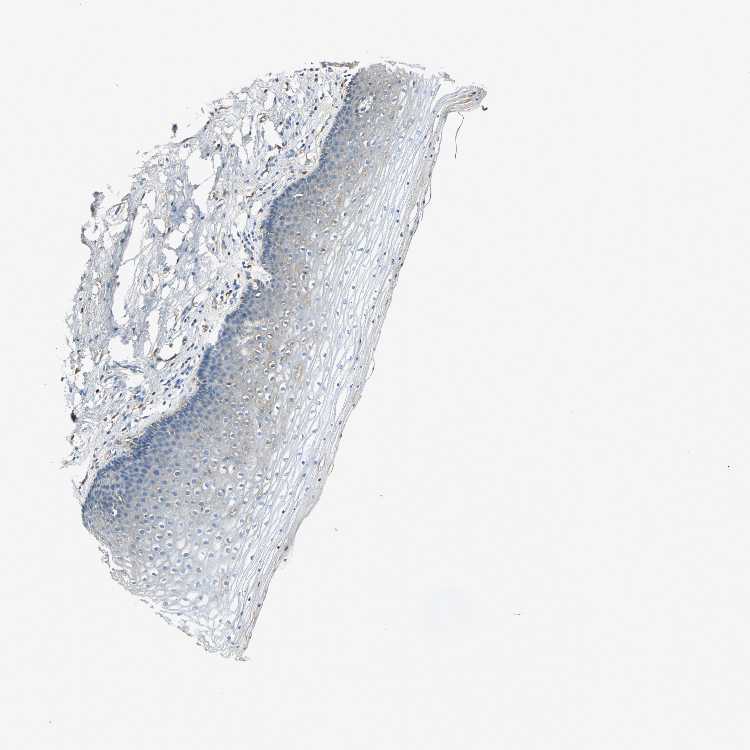

TISSUE PRIMARY DATA CERVIX Show tissue menu

CERVIX - Antibody stainingi

Antibody staining in the annotated cell types in the current human tissue is reported as not detected, low, medium, or high, based on conventional immunohistochemistry profiling in selected tissues. This score is based on the combination of the staining intensity and fraction of stained cells.

Each image is clickable and will lead to virtual microscopy that enables deeper exploration of all samples and also displays staining intensity scores, fraction scores and subcellular localization as well as patient and tissue information for each sample.

Antibody HPA001217Antibody HPA006013

Glandular cells Not detectedNot detected

Squamous epithelial cells -Low